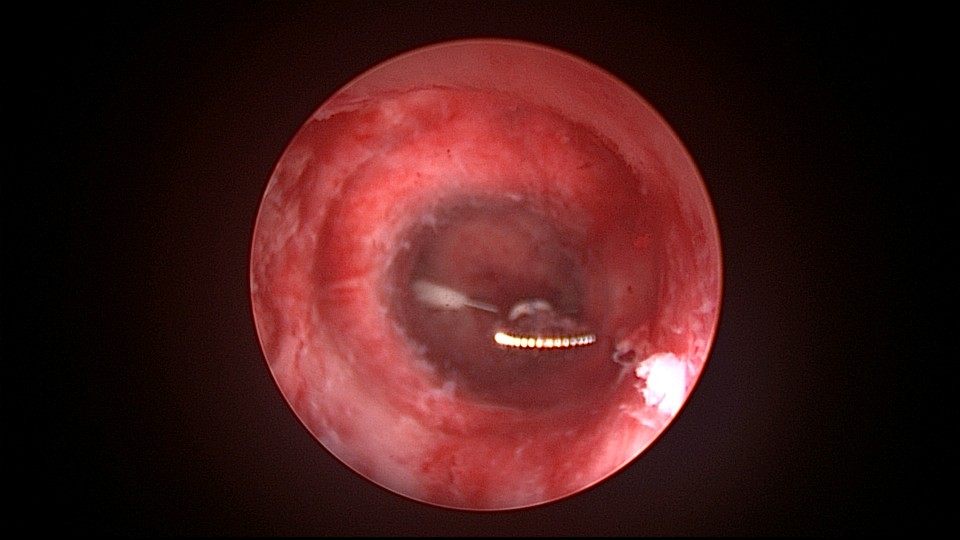

患者38岁,G5P1,剖宫产1次。2023年1月节育环下移带环受孕,宫腔镜取环终止妊娠,同时行左手上臂内侧皮埋避孕,遗憾的是手术医生术中没有找到节育环,术毕复查B超,环仍在宫腔,第二天宫腔镜探查,节育环位于切口憩室内,取出节育环。再次遗憾的是取环后阴道淋漓不净出血,术后第24天复查B超见胚物残留,第三次宫腔镜手术清除残留组织。2025年10月取出皮埋棒,2025年11月外院安环,术后2周复查B超环下移,2025年12月(月经干净3天后),安环医院取出节育环,取环后第6天到我院行宫腔镜安环并做节育环固定。子宫水平位,宫深8.5cm,见切口憩室比宫腔更宽大,形成类似金字塔形状(2次节育环下移原因),行宫腔镜下缝合线结固定节育环,打了3个结,拉过缝合点2个结。第十七例节育环固定。既往带环受孕,多次宫腔镜手术。术后2周复查B超,节育环位置正常,环顶端距宫底1.6cm。